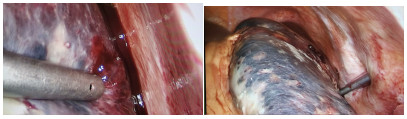

A case of primary splenic angiosarcoma

SILECCHIA G, BORU CE, FANTINI A, et al. Laparoscopic splenectomy in the management of benign and malignant hematologic diseases[J]. JSLS, 2006, 10(2): 199-205.